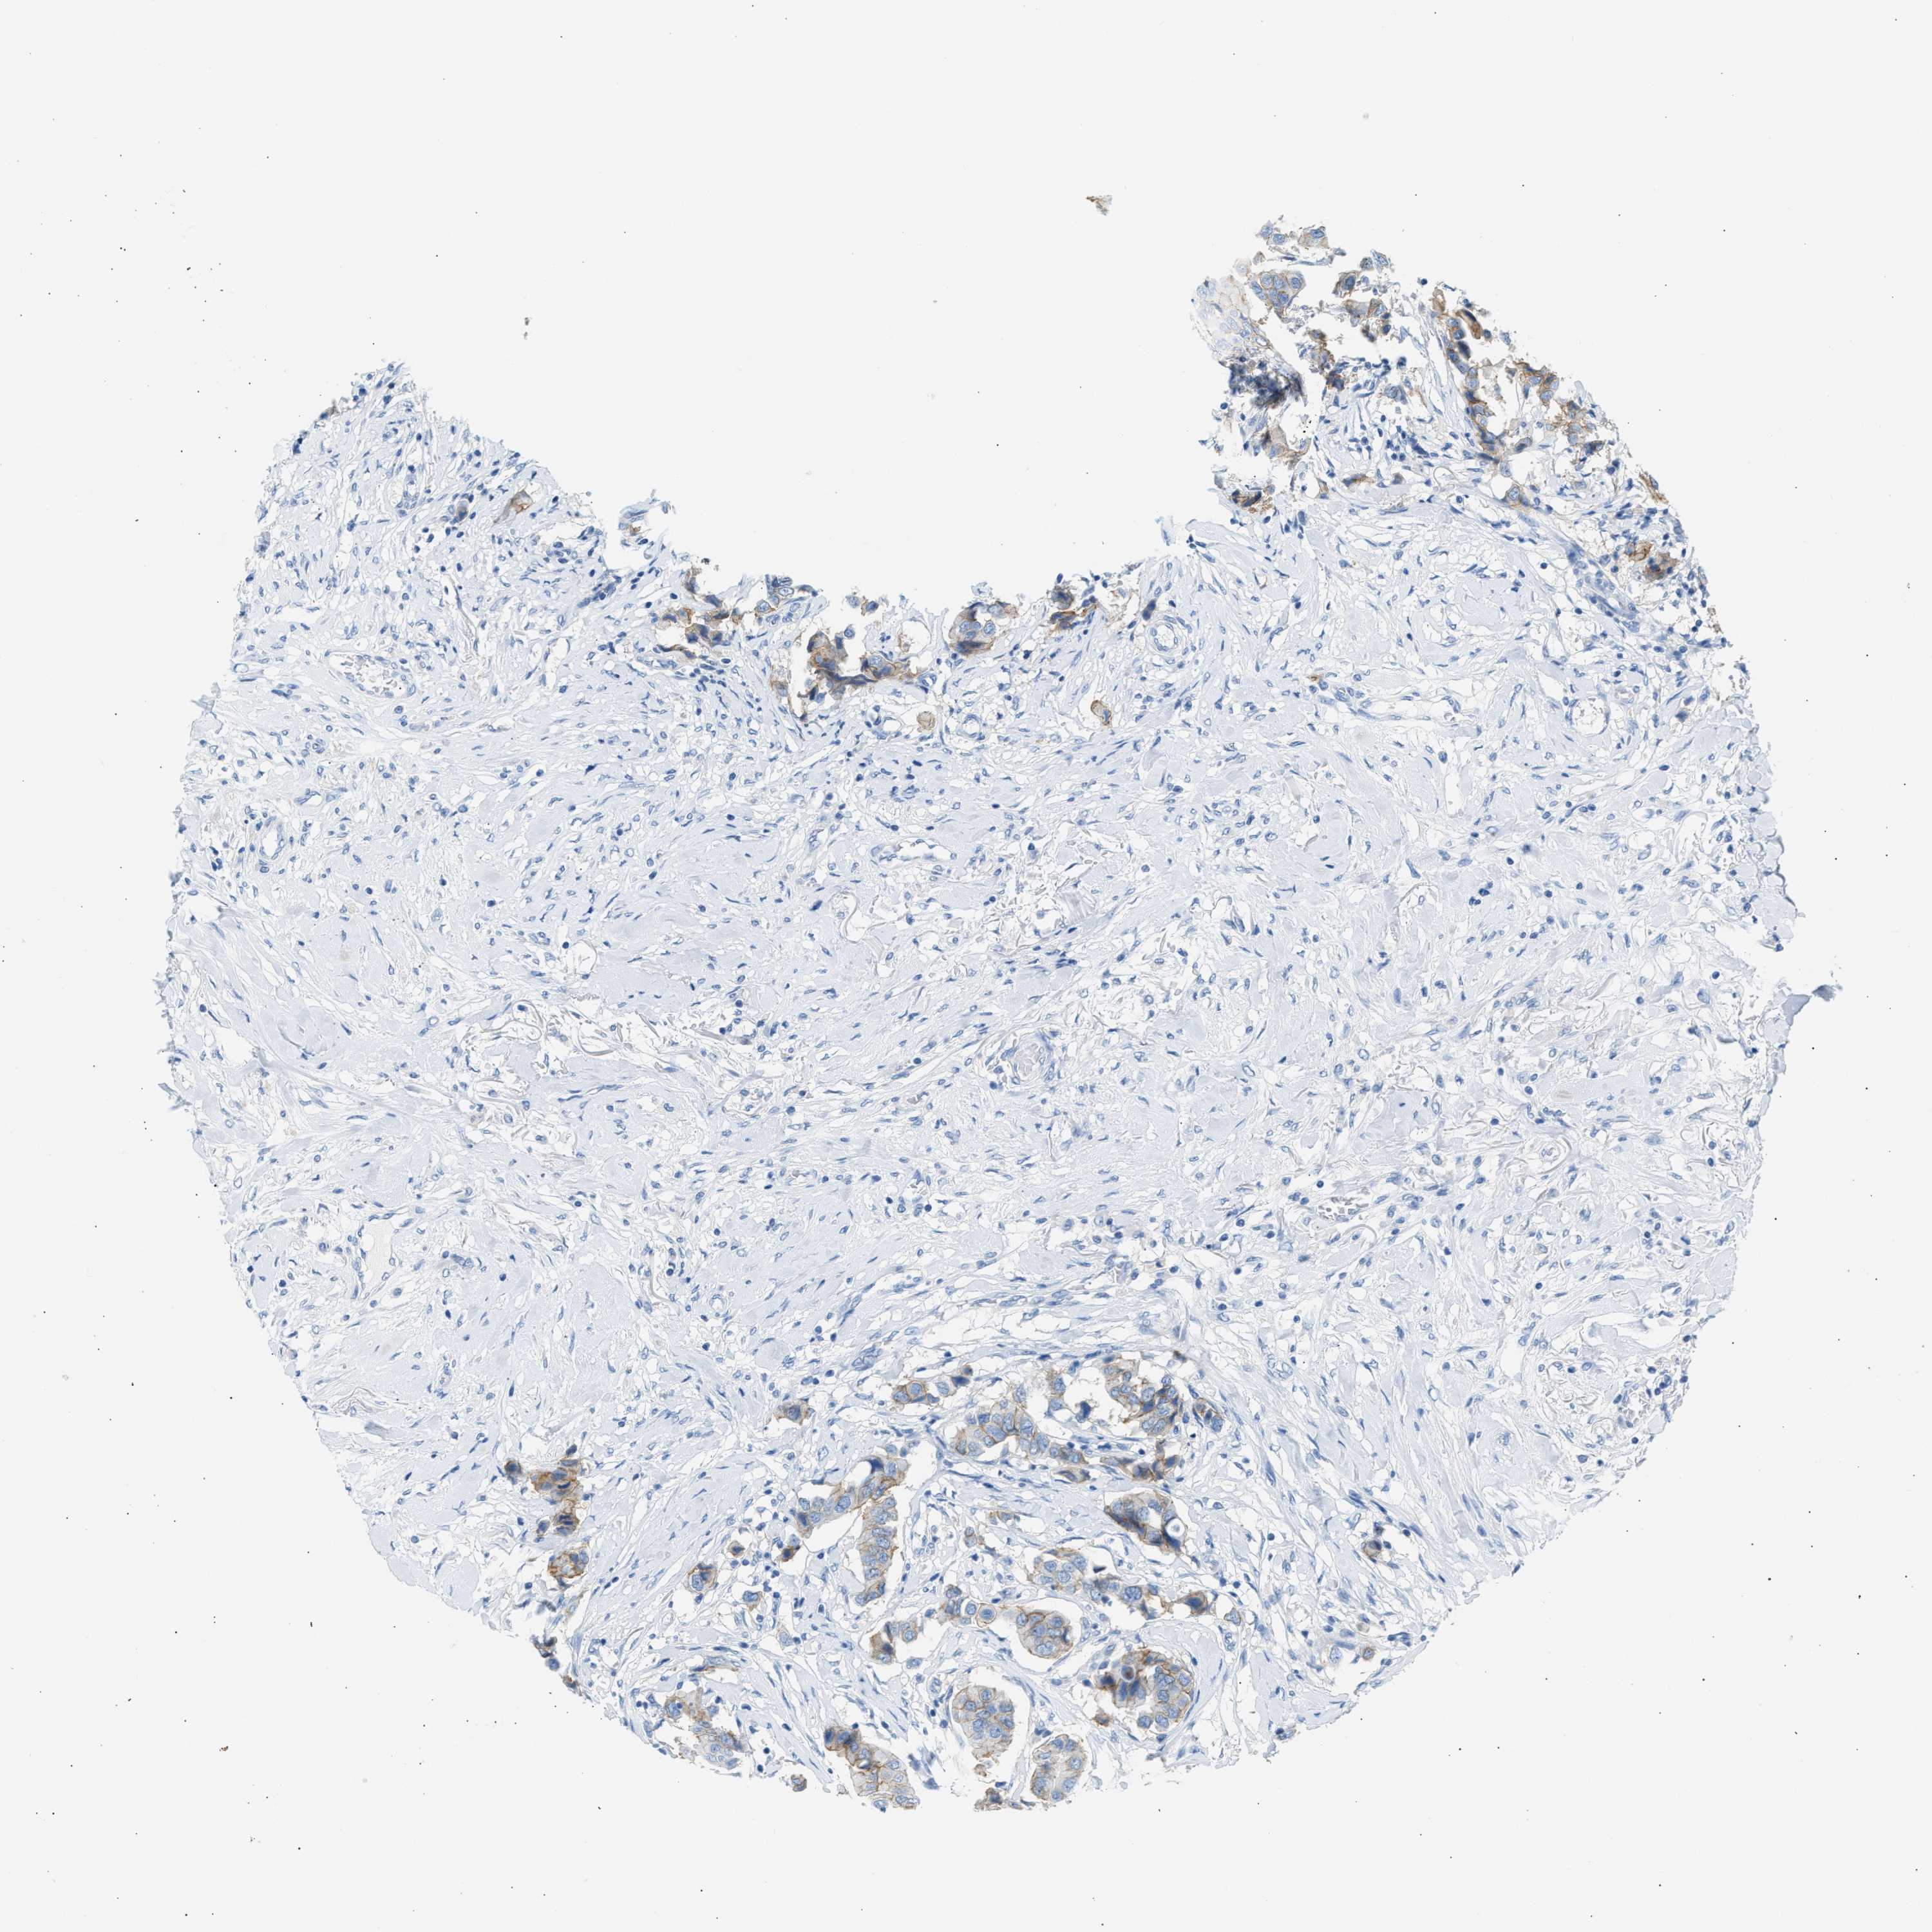

CANCER BREAST CANCER Show tissue menu

BRCA TCGA BRCA VALIDATION PROTEIN EXPRESSION

Breast cancer

Human cancer